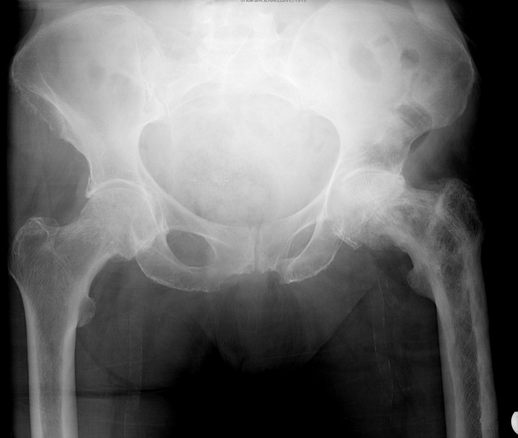

What is the diagnosis and what are the characteristic x-ray findings of this diagnosis?

1) Pelvic Discontinuity

2) X-Ray findings: